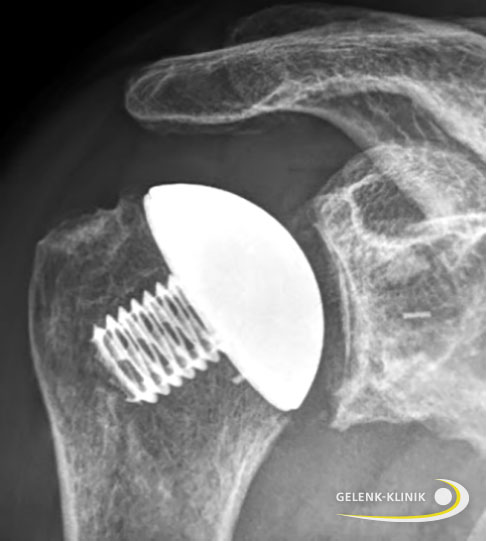

Schulterprothese: Behandlung von schwerer Omarthrose

Bei schwerer Omarthrose empfehlen Spezialisten den Einsatz einer Schulterprothese zur Wiederherstellung schmerzfreier Beweglichkeit der Schulter. Die verschlissenen Gelenkanteile von Oberarmkopf und Schulterpfanne können durch ein künstliches Gelenk ersetzt werden.

Grundsätzlich erhält der Operateur beim Verschleiß des Schultergelenks so viel Knochensubstanz wie möglich. Ist die Rotatorenmanschette intakt, setzt der Schulterspezialist vor allem Kappenprothesen mit Glenoidersatz ein. Den Verzicht auf eine künstliche Pfanne (Glenoidersatz) empfehlen die Orthopäden der Gelenk-Klinik nicht, da die Operationsergebnisse erfahrungsgemäß mittel- bis langfristig schlechter sind.

In Fällen, bei denen die Rotatorenmanschette und insbesondere die Supraspinatussehne geschädigt ist, wählt der Orthopäde eine sogenannte inverse (umgekehrte) Schulterprothese: Der Prothesenkopf befindet sich dabei am Schulterblatt und die Gelenkpfanne wird am Oberarmkopf eingesetzt. Durch diese Umkehr der ursprünglichen Anatomie wird das Drehzentrum des Schultergelenks verändert. Der Deltamuskel kann nun den Arm auch ohne die Hilfe der Sehnen der Rotatorenmanschette bewegen. Dieses Modell eignet sich auch für den Wechsel (Revision) von kleineren Kappenprothesen.